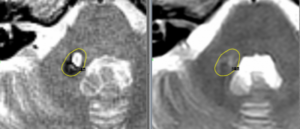

Ангиома гортани

Неприятные ощущения во рту, при глотании пищи, охриплость голоса и кашель, могут свидетельствовать о развитии распространенного недуга — ангиомы гортани. Это заболевание относится к доброкачественным опухолям. Для болезни характерно медленное развитие, поэтому ангиому легко вылечить на начальных стадиях. Угрозы для жизни образование не несет, но обследование у отоларинголога обязательно. Ангиома гортани может давать о себе …